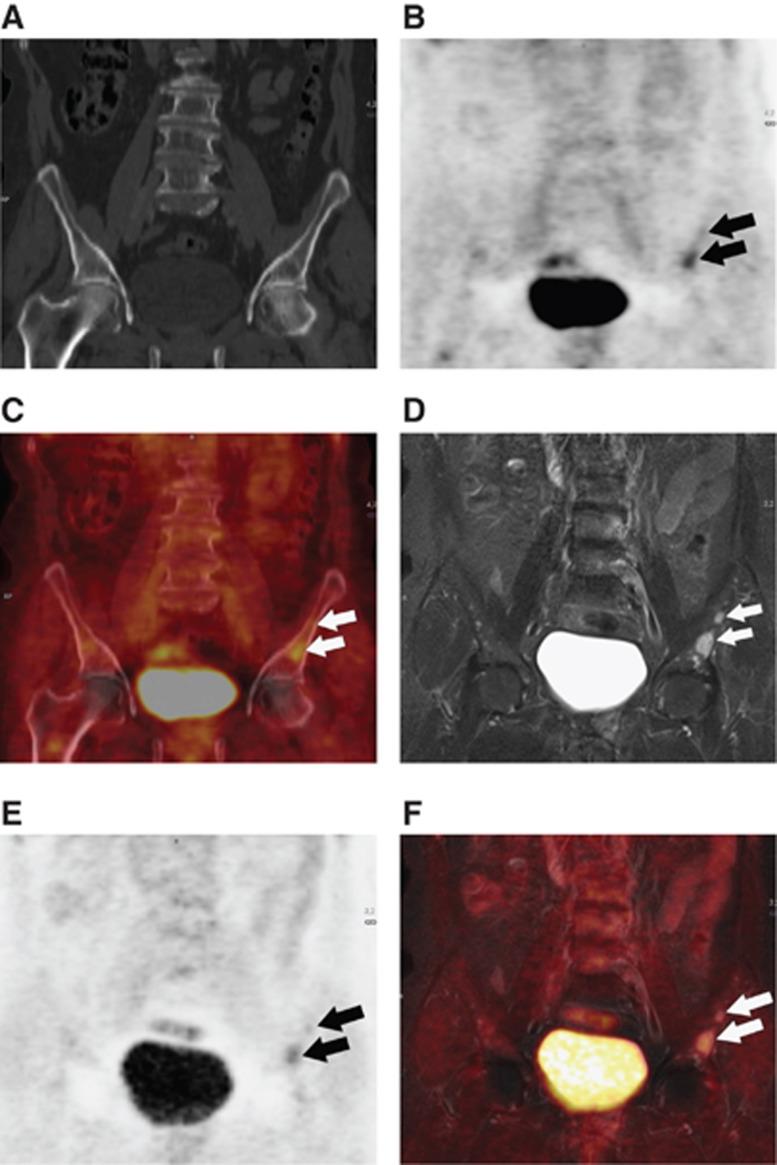

Despite improvements in treatments, metastatic breast cancer remains difficult to cure. Bones constitute the most common site of first-time recurrence, occurring in 40-75% of cases. Therefore, evaluation for possible osseous metastases is crucial. Technetium 99 ((99)Tc) bone scintigraphy and fluorodexossyglucose (FDG) positron emission tomography (PET)-computed tomography (PET-CT) are the most commonly used techniques to assess osseous metastasis. PET magnetic resonance (PET-MR) imaging is an innovative technique still under investigation. We compared the capability of PET-MR to that of same-day PET-CT to assess osseous metastases in patients with breast cancer.

Osseous metastases affected 25 out 109 patients. Metastases were demonstrated by CE-PET-CT in 22 out of 25 patients (88%±7%), and by CE-PET-MR in 25 out of 25 patients (100%). CE-PET-CT revealed 90 osseous metastases and CE-PET-MR revealed 141 osseous metastases (P<0.001). The estimated sensitivity of CE-PET-CT and CE-PET-MR were 0.8519 and 0.9630, respectively. The estimated specificity for CE-FDG-PET-MR was 0.9884. The specificity of CE-PET-CT cannot be determined from patient-level data, because CE-PET-CT yielded a false-positive lesion in a patient who also had other, true metastases.

CE-PET-MR detected a higher number of osseous metastases than did same-day CE-PET-CT, and was positive for 12% of the patients deemed osseous metastasis-negative on the basis of CE-PET-CT.